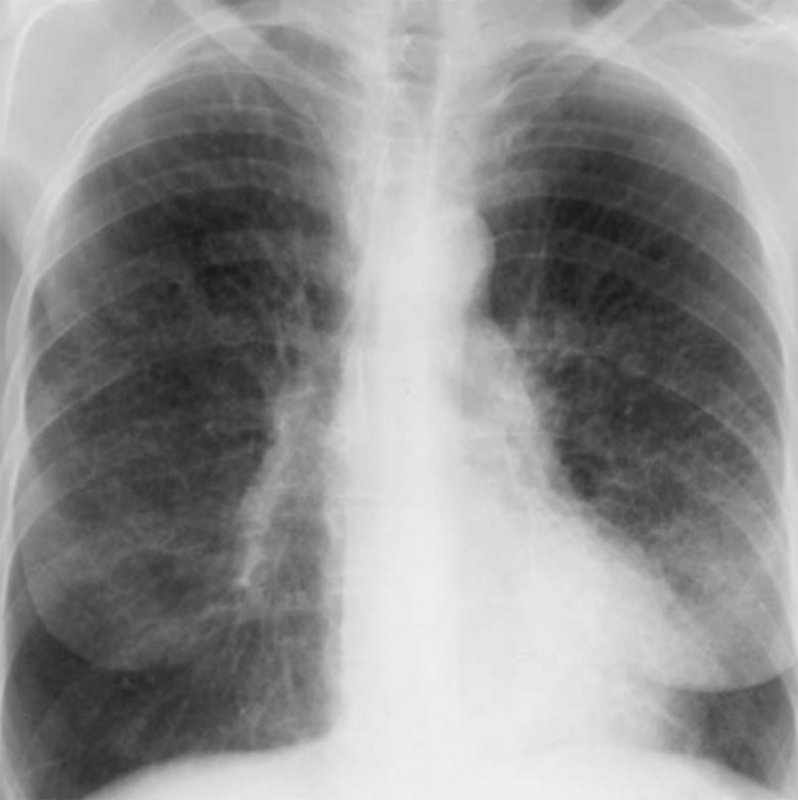

Синдром Гудпасчера – системный капиллярит, характеризующийся преимущественным поражением базальных мембран гломерулярного аппарата по типу гломерулонефрита (с гематурией) и альвеол легких по типу геморрагического пневмонита (с легочными кровотечениями). Рентгенологическая картина характеризуется появлением участков альвеолярной инфильтрации в легких. На рисунке 3 продемонстрированы интерстициальные изменения в легких, характерные для этой патологии.

Рисунок 3. Синдром Гудпасчера: Интерстициальные изменения в легких. Усиление интерстициального компонента легочного рисунка с обеих сторон, определяются ретикулярные и множественные мелкоочаговые тени. Изменения наиболее выражены в нижних и средних отделах легочных полей